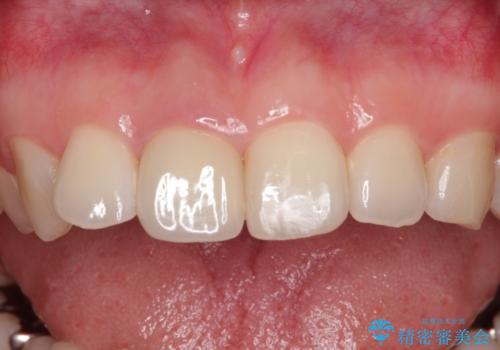

根管治療された状態に大きな問題はなかったため、土台を植立し、オールセラミッククラウンにて補綴治療を行うこととしました。

オーダーメイドタイプのクラウンを選択されたため、周辺の歯と調和が取れる色合いとなるまで修正を繰り返しました。